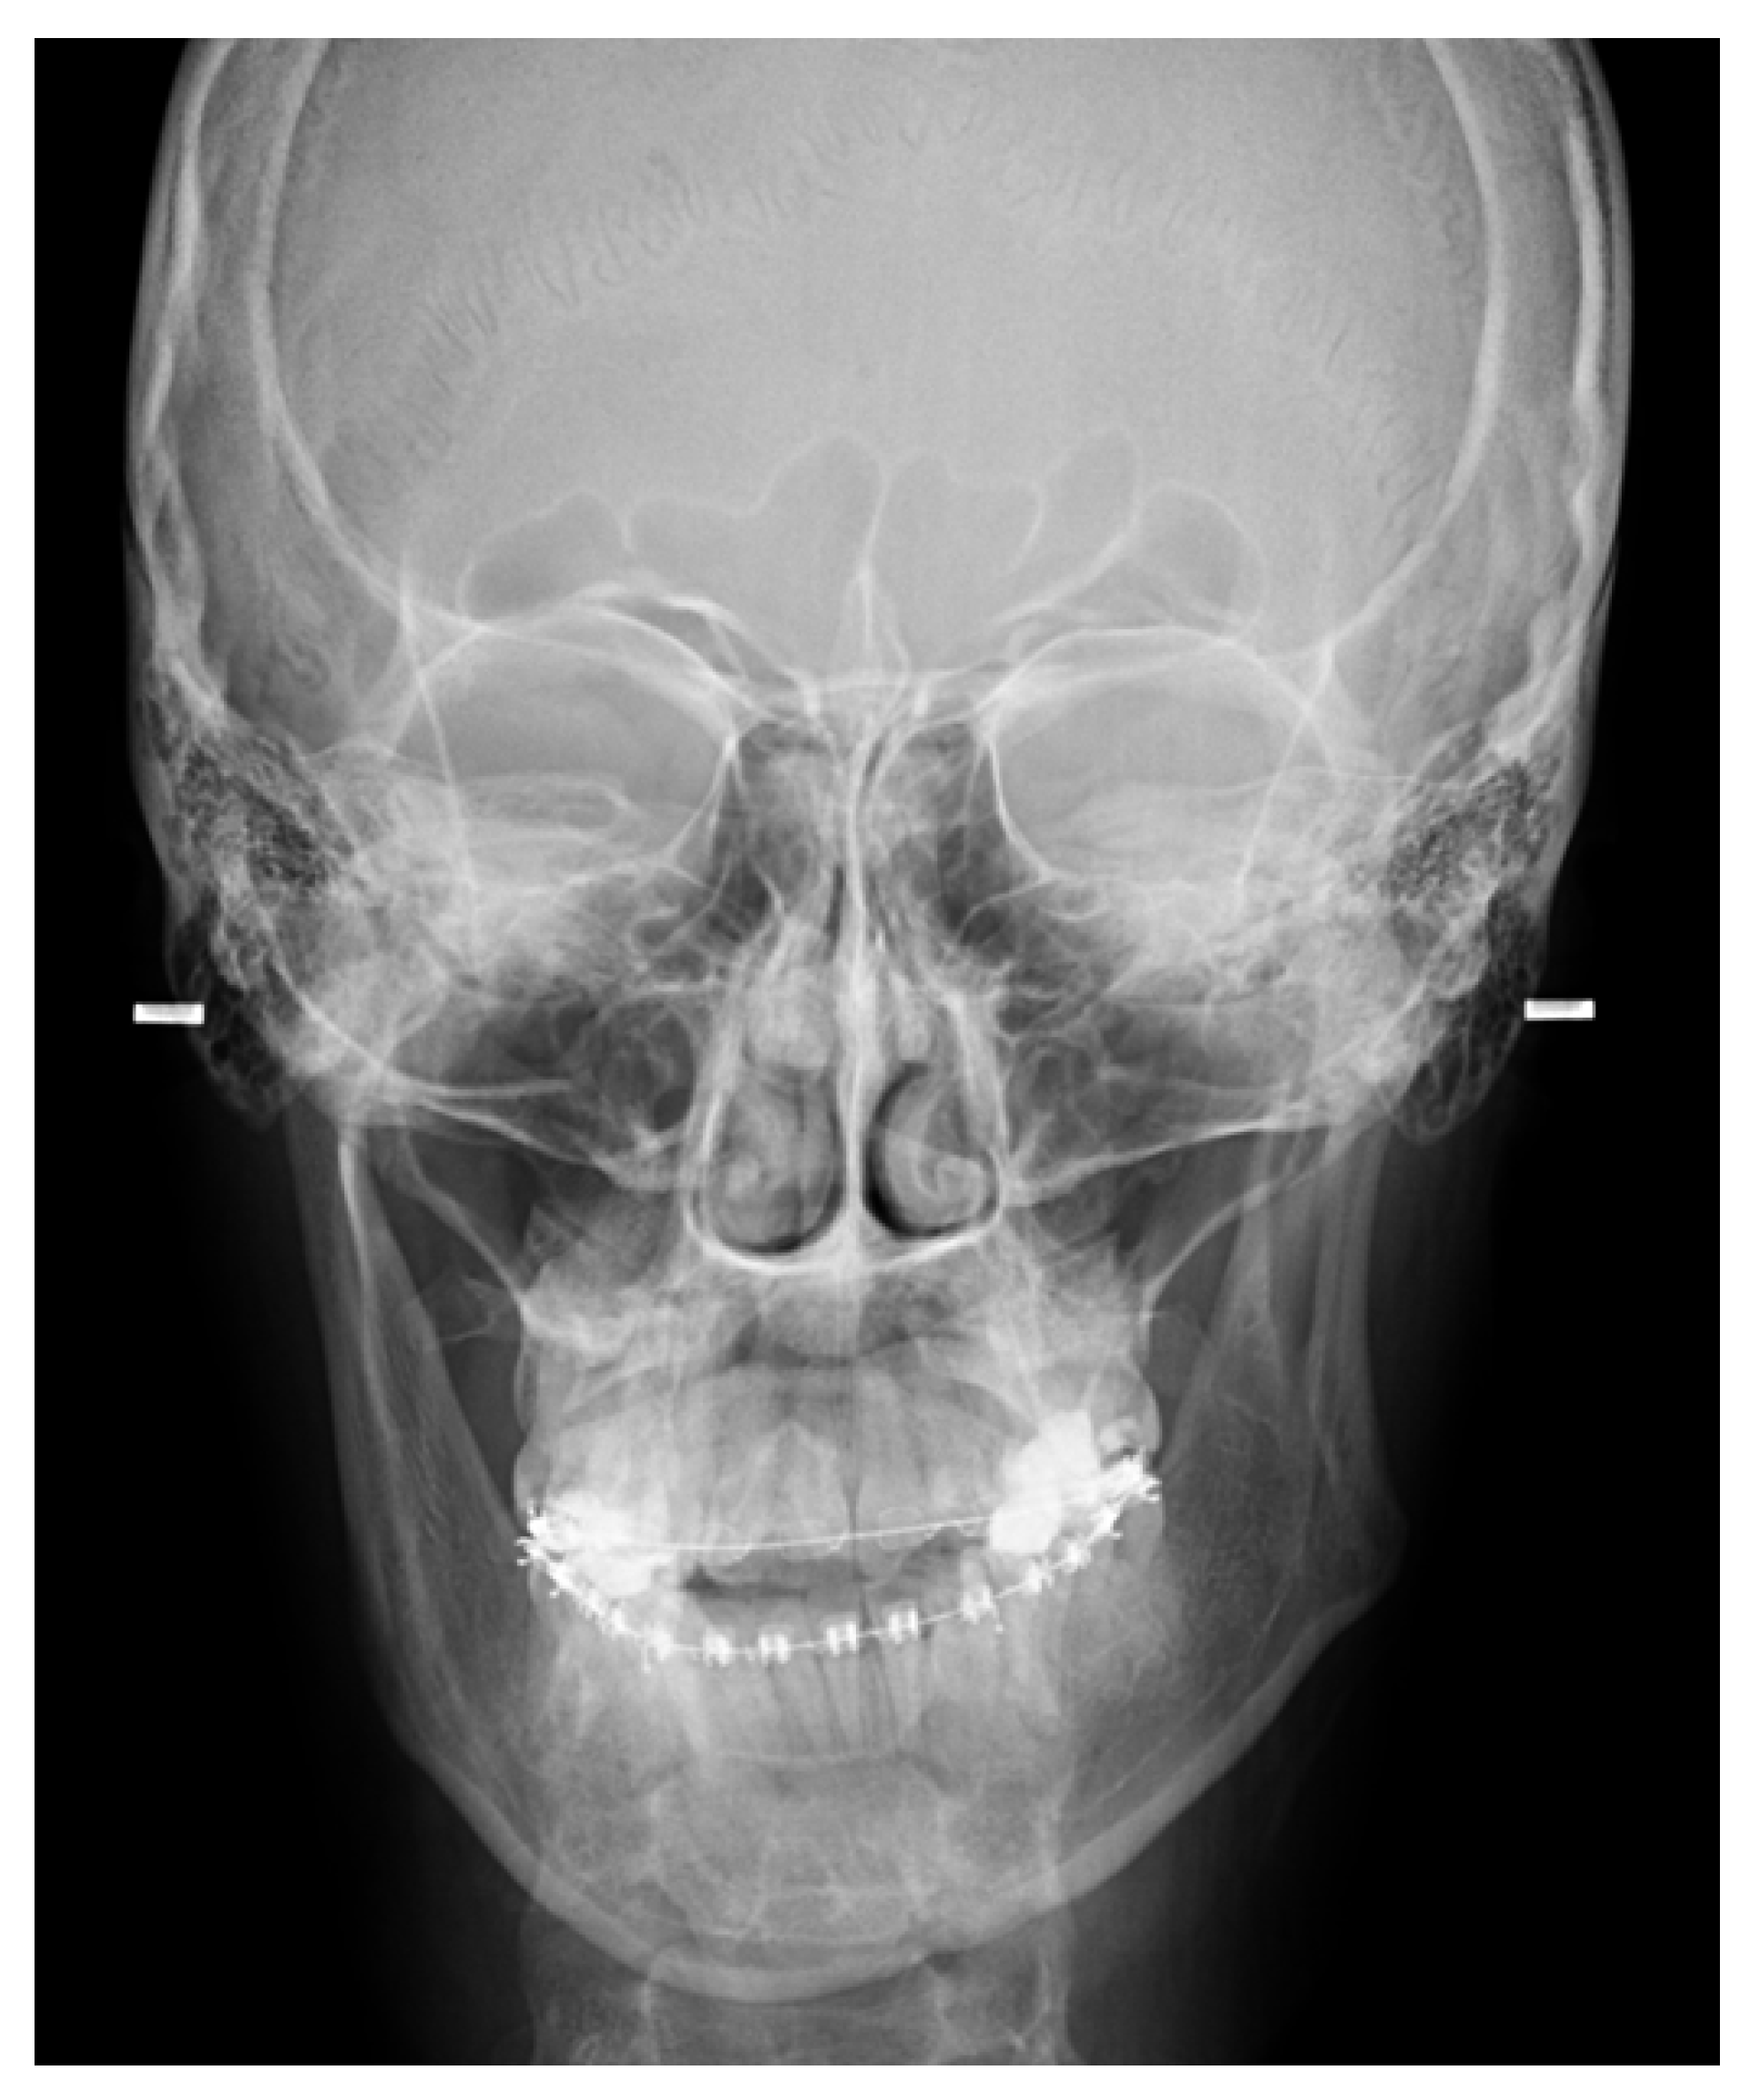

- A condylectomy with BSSO and Lefort I simultaneously was described by Wolford in 2002; however, some authors report operated TMJ joint instability, which might be related to the degree of excised bone and poor condyle stabilization with at least lateral pterygoid muscle reattachment or other, perhaps even related with IMF intramaxillary fixation devices to stabilize the occlusion [75] (Figure 9);